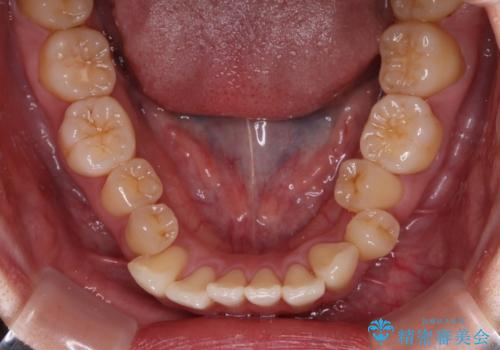

- 上下前歯のデコボコやクロスバイトを気にして来院された患者様です。

上顎歯列が下顎の歯列に対して狭小であり、一部下顎の奥歯が上顎よりも外側に位置している状態でした。